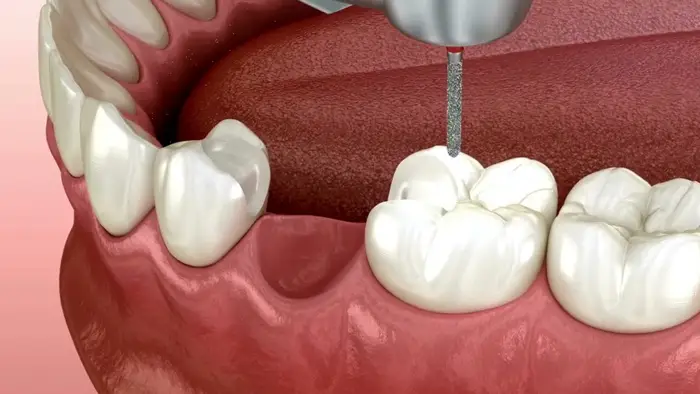

بریجها به دندانهای مجاور متصل میشوند و جای خالی دندانهای از دست رفته را پر میکنند. آنها روی جای خالی یک پل ایجاد میکنند و یک ردیف دندان را بازسازی میکنند. جای خالیهای ایجاد شده توسط بریجها طبیعی به نظر میرسند. این روش سادهتر از ایمپلنتها است و نیازی به جراحی ندارد.

با این حال، دندانهای پشتیبان ساییده میشوند که باعث ضعیف شدن آنها میشود. جای خالیهای ایجاد شده توسط دندانهای از دست رفته به سرعت پر میشوند. بریجها به همان مراقبت دندانهای طبیعی نیاز دارند. آنها در مقایسه با ایمپلنتها مقرون به صرفه هستند. نکته منفی، احتمال فشار بر ساختارهای پشتیبان است. آنها برای جای خالیهای کوچک ایجاد شده توسط دندانهای از دست رفته مناسب هستند. جدول زیر خلاصه مزایا و معایب بریج را به تصویر کشانده است:

| بازگرداندن زیبایی: جایگزین کردن دندان از دست رفته و بهبود ظاهر لبخند و صورت. | نیاز به تراشیدن دندانهای سالم: دندانهای مجاور (اباتمنت) باید تراشیده شوند تا بریج روی آنها قرار گیرد، که این امر ساختار سالم دندان را کاهش میدهد. |

| بهبود عملکرد جویدن و گفتار: پر کردن شکاف، امکان جویدن مناسبتر و تلفظ صحیح کلمات را فراهم میکند. | افزایش خطر پوسیدگی: اگر بریج به درستی چسبانده نشود یا بهداشت دهان ضعیف باشد، دندانهای زیر بریج یا در محل اتصال ممکن است دچار پوسیدگی شوند. |

| پایداری ساختار فک: جلوگیری از جابهجایی، کج شدن یا بیرون زدن دندانهای باقیمانده به سمت فضای خالی. | فشار بر دندانهای تکیهگاه (اباتمنت): بریج وزن نیروی جویدن را بر دندانهای مجاور تقسیم میکند که میتواند در طول زمان باعث تضعیف یا آسیب به آنها شود. |

| سرعت و سادگی درمان: معمولاً در مقایسه با ایمپلنت دندان، فرآیند درمانی سریعتر و سادهتری دارد (معمولاً در چند جلسه). | عمر محدود: بریجهای دندانی معمولاً نیاز به تعویض دارند (به طور میانگین ۵ تا ۱۵ سال)، در حالی که ایمپلنت میتواند طول عمر بیشتری داشته باشد. |

| گزینهای مناسب برای افراد خاص: میتواند برای افرادی که کاندیدای مناسبی برای ایمپلنت دندان نیستند (مثلاً به دلیل عدم وجود استخوان کافی) یک راهکار باشد. | نیاز به مراقبت ویژه: تمیز کردن زیر بخش مصنوعی بریج (پونتیک) نیاز به ابزارهای خاص مانند نخ دندان مخصوص (Floss Threader) دارد و کمی دشوارتر است. |

| هزینه اولیه کمتر: معمولاً هزینه اولیه بریج دندان نسبت به ایمپلنت کمتر است. | جلوگیری نکردن از تحلیل استخوان فک: برخلاف ایمپلنت، بریج ریشه دندان را تحریک نمیکند و با گذشت زمان، استخوان فک زیر ناحیه دندان از دست رفته ممکن است تحلیل برود. |